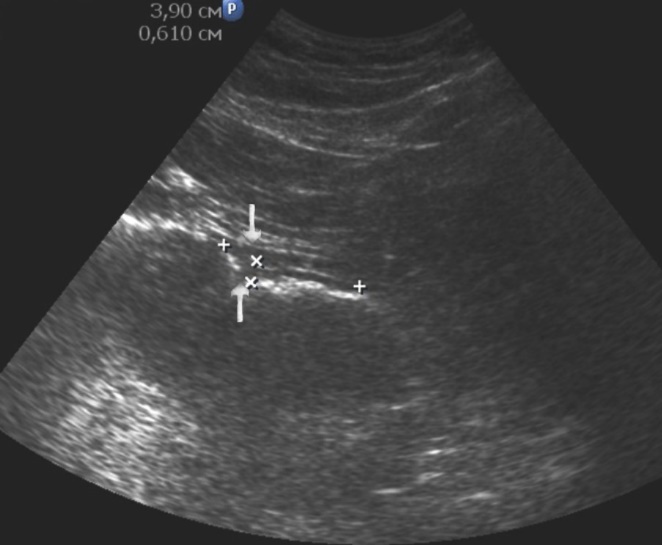

Distal gastric cancer was observed in 24 (39,3%) cases and contributed to the development of pyloric stenosis: in 6 (9,8%) cases it was compensated, in 18 (29,5%) – was sub compensated. The layers of the wall were not differentiated in all patients with sub compensated pyloric stenosis. In the case of compensated pyloric stenosis, the thickness of the affected area was 10,2±2,9mm, the length was 27,1±6,2mm, the diameter of the pylorus was 8,3±0,8mm (Figure 14). Among patients with sub compensated pyloric stenosis, the thickness of the stomach wall was 19,8±4,1mm, the length was 43,6±4,5mm, the pyloric diameter was 4,3±1,1mm (Figure 15).

Figure 14.Gastric carcinomas of diffuse infiltrative form in the atrium of T2 stage. Compensated pyloric stenos. On an empty stomach in the cavity of the stomach is determined an a small amount of fluid. The diameter of the pyloric canal more than 7 mm.

Figure 15.Distal gastric carcinomas of diffuse infiltrative form of T3 stage. Sub compensated pyloric stenos (arrows). The thickness of the anterior wall of the stomach is 9,13 mm, extent of the affected area – 7,84 cm. On an empty stomach in the cavity of the stomach is determined an a large amount of fluid. The diameter of the pyloric canal is about 6 mm.